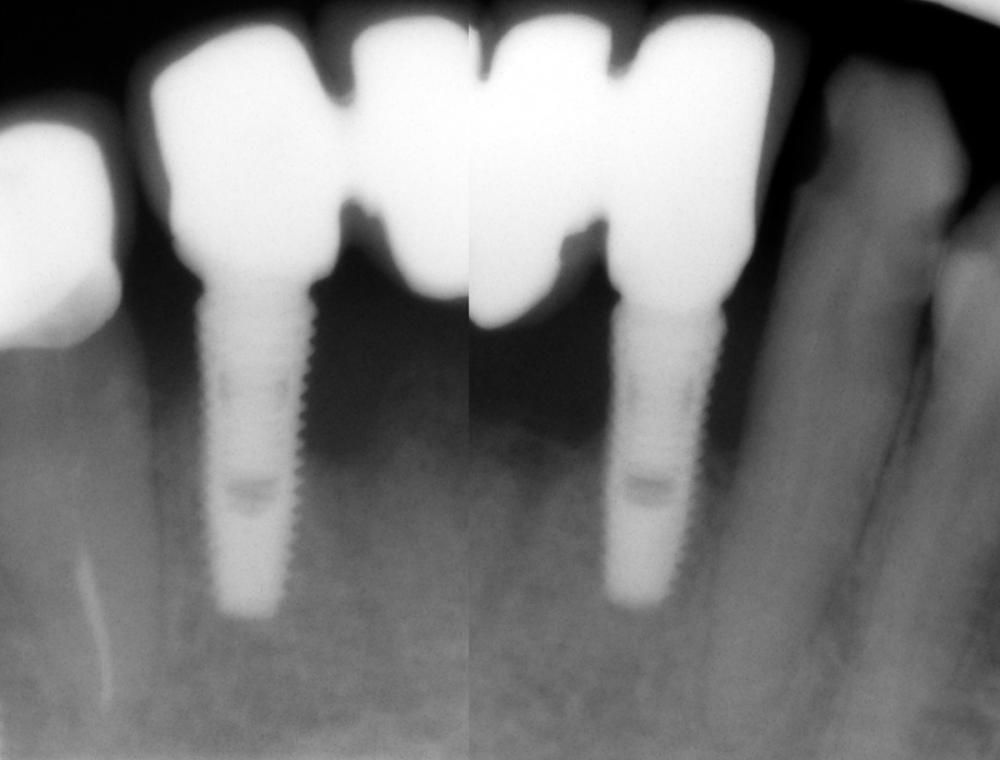

dentikl Опубликовано 1 июня, 2021 Поделиться Опубликовано 1 июня, 2021 а рентген есть? Ссылка на комментарий

Карен Аванесов Опубликовано 1 июня, 2021 Автор Поделиться Опубликовано 1 июня, 2021 6 часов назад, dentikl сказал: а рентген есть? Ссылка на комментарий